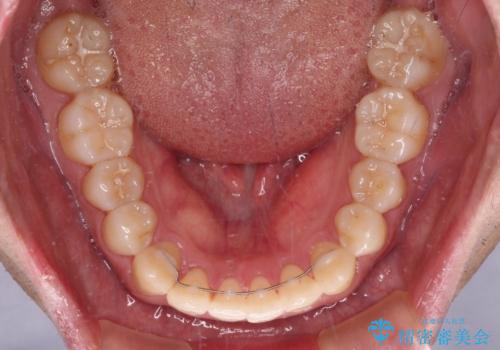

インビザラインで奥歯の咬み合わせと前歯のデコボコを改善

インビザライン単体では右側の交叉咬合を解消することができなかったため、アンカースクリューを併用して咬合を改善させました。